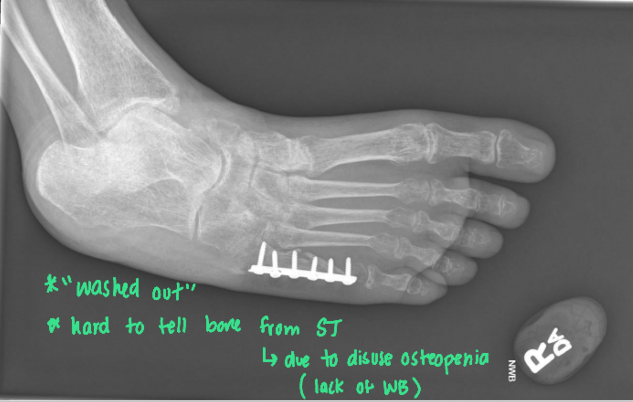

Bone Density: What are the components you are examining?

• General and focal BD (contrast between ST and bone + cortical shell and cancellous center)

• Loss of contrast means we are losing density

• Localized contrast changes

• Look for sclerosis (excessive/reactive) or spurs

• This can happen due to fx, osteomyelitis, OA, or tumors \

• Texture (normal trabecular architecture)

• Thin, delicate, coarse, lacy, fluffy

<ul><li><p><span style="color: red;"><strong>General and focal BD</strong></span> <strong><mark data-color="green" style="background-color: green; color: inherit;">(contrast between <u>ST and bone </u>+ <u>cortical shell and cancellous center) </u></mark></strong></p><ul><li><p>Loss of contrast means we are <strong><mark data-color="red" style="background-color: red; color: inherit;"><u>losing density</u></mark></strong></p></li></ul></li><li><p><span style="color: red;"><strong>Localized contrast changes</strong></span></p><ul><li><p>Look for <span style="color: red;">sclerosis (excessive/reactive) or spurs</span><strong> </strong></p></li><li><p>This can happen due to <em><mark data-color="red" style="background-color: red; color: inherit;"><u>fx, osteomyelitis, OA, or tumors \</u></mark></em></p></li></ul></li><li><p><span style="color: red;"><strong>Texture</strong></span> <strong><mark data-color="green" style="background-color: green; color: inherit;">(normal trabecular architecture)</mark></strong></p><ul><li><p>Thin, delicate, coarse, lacy, fluffy</p></li></ul></li></ul><p></p>